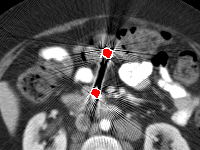

Effect of metal mask projection (SE0-Net vs SE-Net). From Table 1, we can observe the use of instead of improves the performance for at least 4.1 dB in PNSR and reduces MSE from 0.95219 to 0.00074 for all metal sizes. The groups with large metal implants benefit more than groups with small metal implants. As shown in Fig. 4, the artifacts in metal trace of SE0-Net are over-removed or under-removed, which introduces bright and dark bands in the reconstructed CT image. With the help of , SE-Net can suppress the artifacts even when the metallic implants are large and the surrogate data are more consistent with the correct data outside the metal trace.

Effect of sinogram padding (SE-Net vs SEp-Net). Sinogram padding mainly improves the performance in the group with the largest metal objects, with a PSNR gain of 0.15 dB and an MSE reduction of 0.00048. As shown in Fig. 4, the model with sinogram padding restores finer details of soft tissue between large metallic objects because more correct information is retained by periodic padding than zero-padding.

Effect of learning with (SEp-IE-Net vs Ours). When is jointly restored with the corrupted , the sinogram correction performance is affected with an increment of 0.00033 in MSE and of 0.7 dB in PSNR. More details of soft tissue around metal are retained and the image becomes sharper, as shown in Fig. 4.